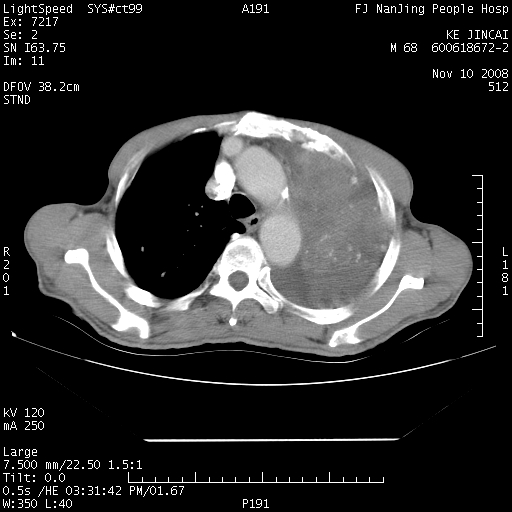

是个很有看头的病例,咋人气那么不旺?没多少人兴趣呢?这个病例几大怪:1   恶性肿瘤侵犯心肌左房怪,心肌一般不会被恶性肿瘤侵犯吧?2   左下肺均匀实变怪,内无含气,有别一般不张实变,含气肺泡完全为液体取代,而非一般不张实变的肺萎陷,冷不丁还以为是肿大的脾脏3   肿瘤本身怪,像tb肺不张4   这么有看头的病例没人气怪。呵呵。

追查病史,咳嗽,患者无发热,血象不高。据说2年前胸片检查怀疑肺ca曾行纤支镜检查,病理未见到癌细胞。无确切资料。

左肺恶性肿瘤侵犯肺动脉,左心房内瘤栓,胸膜转移。